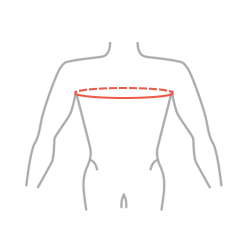

Таблица размеров:

| Размер | Окружность грудной клетки | Способ снятия мерки |

|---|---|---|

| 1 | 40 — 50 см |

|

| 2 | 50 — 60 см | |

| 3 | 60 — 70 см |

ВНИМАНИЕ! Правильный размер подбирается исходя из измерения окружности груди на уровне подмышек.

Таблица размеров:

| Размер | Окружность грудной клетки | Способ снятия мерки |

|---|---|---|

| 1 | 40 — 50 см |

|

| 2 | 50 — 60 см | |

| 3 | 60 — 70 см |

ВНИМАНИЕ! Правильный размер подбирается исходя из измерения окружности груди на уровне подмышек.